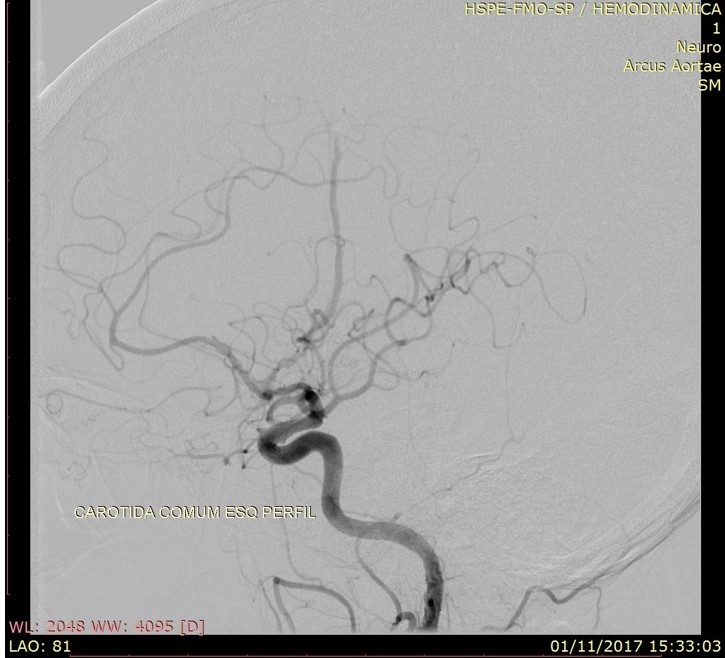

Discussão de tratamento de Fístula Arteriovenosa Dural grau I

Malformações artério venosas durais intracranianas - Discussão de caso fístula dural pós traumática grau I

Fístulas arteriovenosas durais (FAVDs) são lesões adquiridas, que consistem em uma ou mais conexões fistulosas no interior dos folhetos da dura-máter, envolvendo mais especificamente as paredes de um seio venoso dural ou as veias leptomeníngeas adjacentes.

Em 1995, Cognard et al. analisaram retrospectivamente 205 pacientes portadores de FAVDs, atendidos no período de 18 anos, em três grandes centros de referência no mundo. Algumas alterações e complementações foram propostas à classificação estabelecida anteriormente por Djindjian et al.  Na classificação publicada por Cognard et al., as lesões tipo I possuem drenagem diretamente para o interior de um seiovenoso dural, somente de forma anterógrada . As lesões tipo II são caracterizadas por elevada sobrecarga arterial e insuficiente drenagem venosa anterógrada. Ocorre, então, fluxo retrógrado ao longo do seio venoso.  Essa categoria é subdividida em três grupos,incluindo: tipo lIa com fluxo retrógrado somente no interior do seio venoso; tipo Ilb, com fluxo anterógrado no interior do seio venoso e refluxo para as veias corticais; e tipo lIa + b, com fluxo retrógrado para o seio e veias corticais. As lesões tipo III drenam exclusivamente para as veias corticais sem ectasia venosa. As lesões tipo IV drenam diretamente para as veias corticais que possuem ectasia venosa (dilatação maior que 5 mm de diâmetro). Finalmente, Cognard et al.acrescentaram um novo grupo, representado pelas lesões que drenam diretamente para as veias perimedulares espinhais, classificando-as como tipo V.